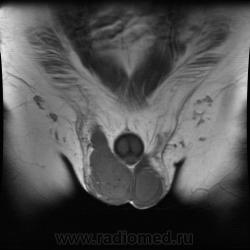

Продолжение УЗИ.

"Мужчина, 60 лет. Около 3 месяцев назад появился дискомфорт в области мошонки, увеличение правого яичка."